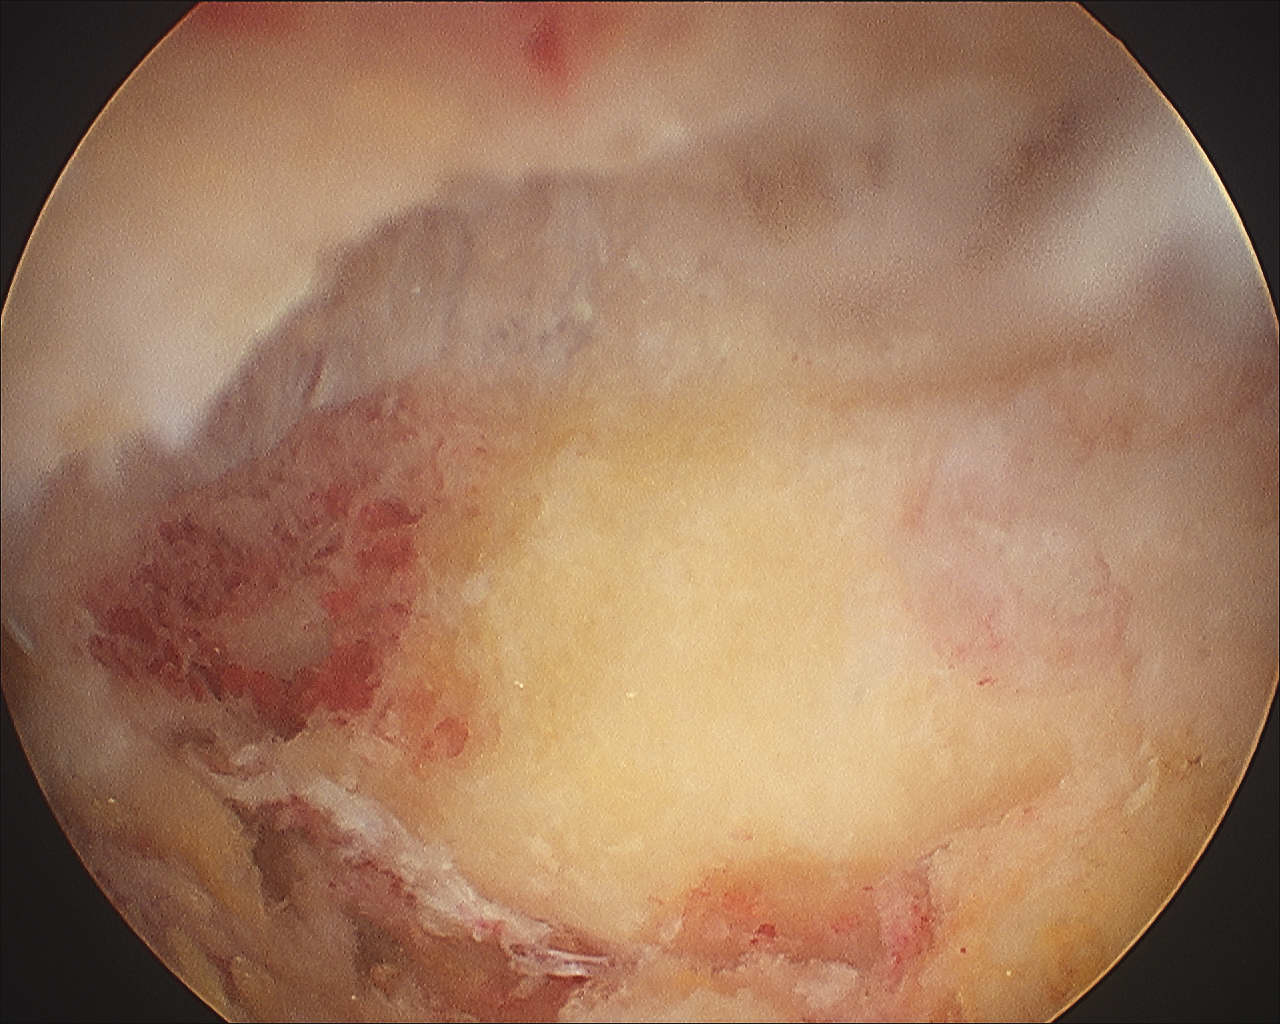

1. Identify distal clavicle

- camera posterior portal, electrocautery lateral portal

- remove bursa in subacromial space

- follow anterior acromion medially with cautery

- identify the distal clavicle (push down on clavicle repetitively)

- clean and identify clavicle anterior and posterior

2. Anterior portal

- placed just at lateral aspect of distal acromion

- in line with AC joint

- remove anterior then posterior clavicle

- must remove full thickness of distal clavicle superiorly / be able to visualise superior AC ligament

- must not leave posterior edge

- can place camera in lateral portal to enhance view